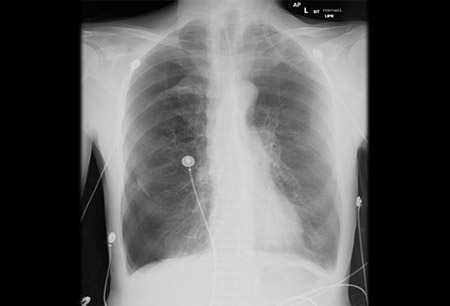

- chest x-ray